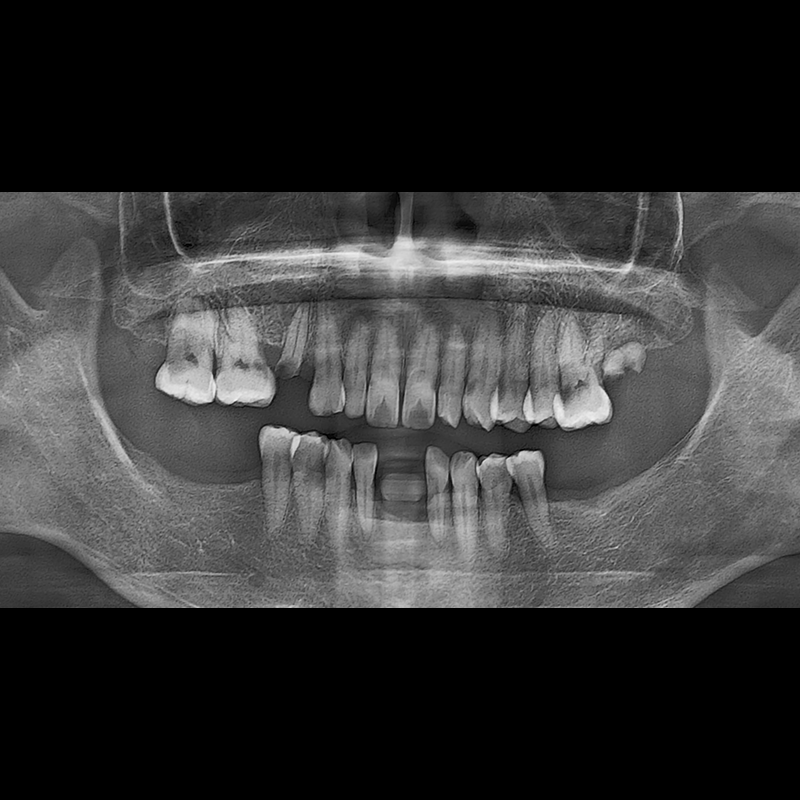

BEFORE AFTER

インプラント手術事例 2025.05.30

欠損した歯の部分と、生かしにくい歯の位置にインプラントを植立しました。